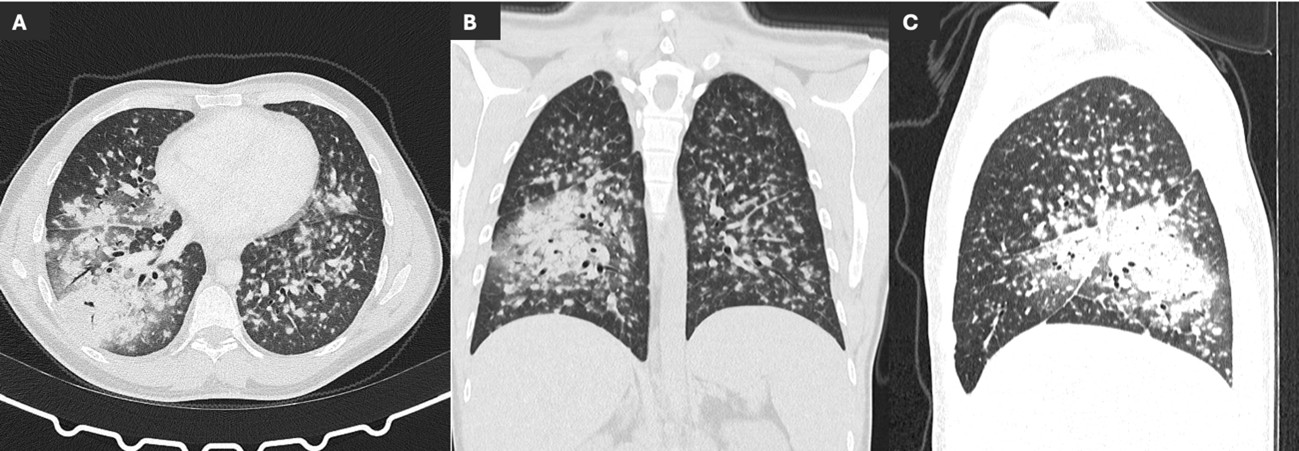

A chest radiograph (Figure 1) and a thoracic computed tomography (CT) were performed, revealing multiple bilateral solid and subsolid nodules, ill-defined and with varying sizes (not exceeding 1 cm), with a tendency to confluence and mostly with a peribroncovascular pattern of distribution, although some juxta-pleural nodules were seen (Figure 2). Additionally, a consolidation on the middle and right lower lobe with air-bronchogram was identified (Figure 2). Multiple enlarged mediastinal and hilar lymph nodes were also present, some with central hypodensity suggestive of necrosis (Figure 3). Pleural effusion was excluded.

Figure 2: Axial (A), coronal (B) and sagittal (C) non-enhanced CT scan showing multiple nodules in both lungs, solid and subsolid, with varying sizes and mostly with a peribroncovascular pattern of distribution, associated with a middle and right lower lobe consolidation.